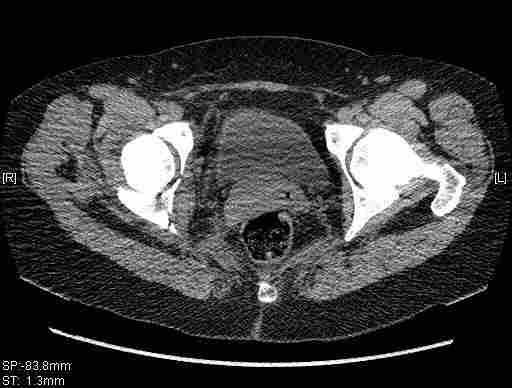

Удалось сегодня вывести пациентку в соседнюю больницу, где есть кт. Срезы сделаны только горизонтальные.

Приветствую,Антон.Рункова рядом нет,но после полученных данных КТ,обсуждали совместно.Итог обсуждения-развернутый ответ дать не получится,т.к.срезы выбраны не информативные.Если ориентироваться на данные 3D,то ,ИМХО,можно лечить на вытяжении.